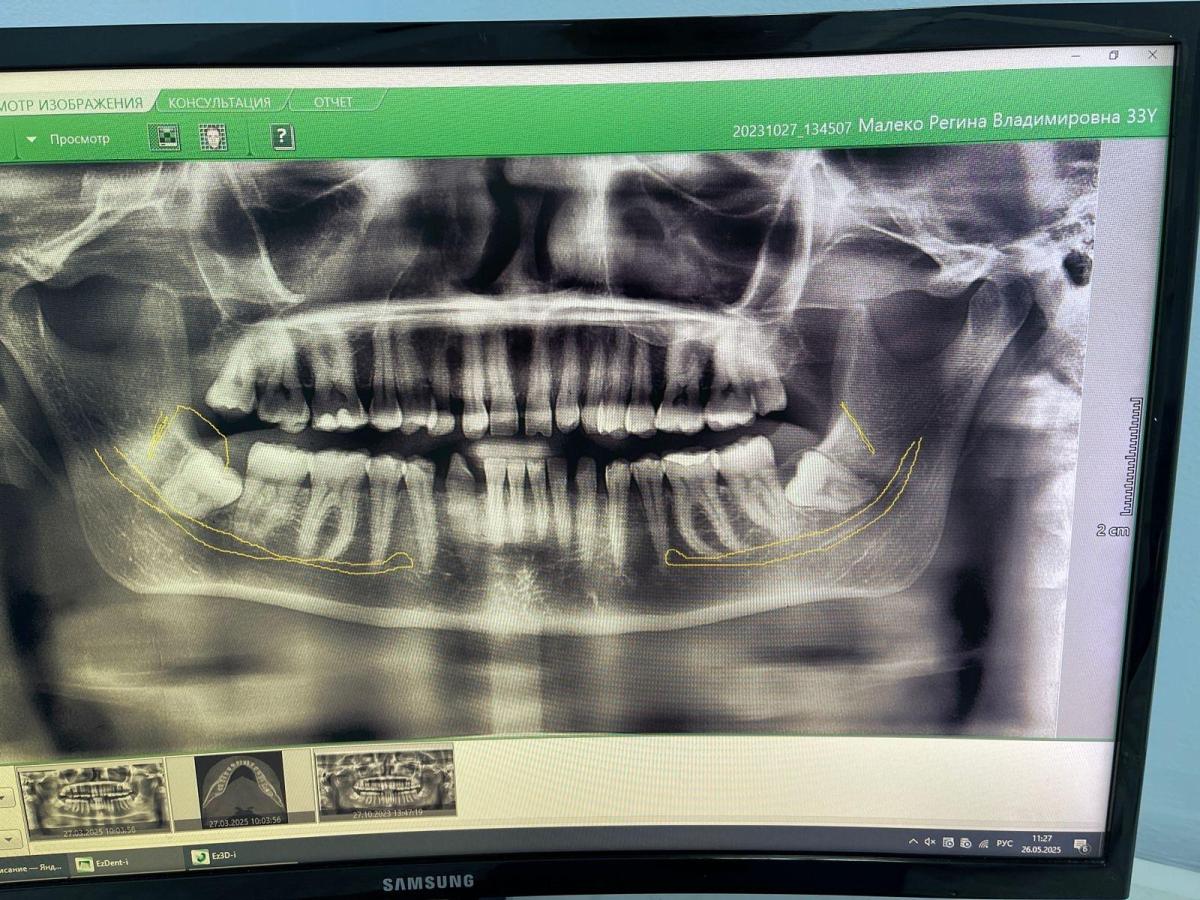

На данный момент состояние зубов на фото.

Я категорически против, чтобы удаляли 3 здоровых зуба!!! Ранее была удалена вверху 6-ка и 3 зуба мудрости.

На последнем приёме врач сказал, что нужно удалить 3 зуба( два пятёрки сверху и внизу одну единичку или двойку) из-за того, что возник дистальный прикус. Хотя месяца 1-2 все было в норме.